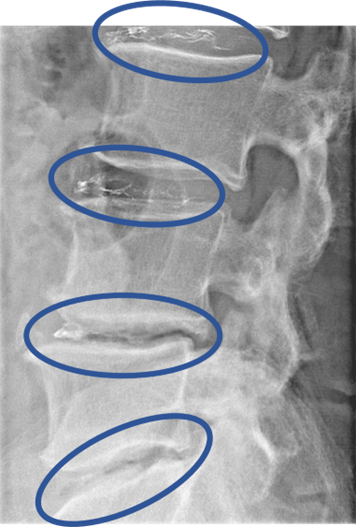

L1/2: 異常なし

L2/3: 椎間板ヘルニア、椎間板変性症

L3/4: 椎間板変性症

L4/5: 椎間板変性症、両椎間孔狭窄

L5/S: 椎間板変性症、両椎間孔狭窄

以上の事が画像上認められます。

L2/3、3/4、4/5、5/sに

椎間板ヘルニア、椎間板変性症、両椎間孔狭窄 を認め、主症状の原因の可能性が高い。